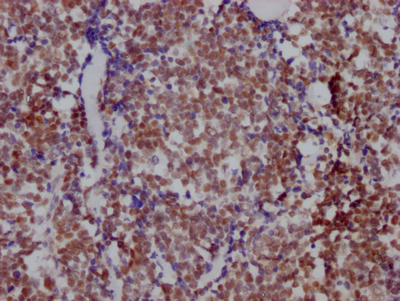

IHC image of CSB-RA906662A0HU diluted at 1:100 and staining in paraffin-embedded human lung cancer performed on a Leica BondTM system. After dewaxing and hydration, antigen retrieval was mediated by high pressure in a citrate buffer (pH 6.0). Section was blocked with 10% normal goat serum 30min at RT. Then primary antibody (1% BSA) was incubated at 4℃ overnight. The primary is detected by a Goat anti-rabbit IgG polymer labeled by HRP and visualized using 0.05% DAB.